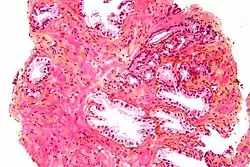

A próstata consiste em tecido glandular e conjuntivo. Células altas em forma de coluna formam o revestimento (o epitélio) das glândulas.[1] Estas formam uma camada ou podem ser pseudoestratificadas.[3] O epitélio é altamente variável e áreas de células cuboidais baixas ou planas também podem estar presentes, com epitélio transicional nas regiões externas dos ductos mais longos.[9] As glândulas são formadas como muitos folículos, que drenam para os canais e, subsequentemente, para 12–20 ductos principais. Estes, por sua vez, drenam para a uretra à medida que passa pela próstata.[3] Há também uma pequena quantidade de células planas, que ficam próximas às membranas basais das glândulas e agem como células-tronco.[1]

O tecido conjuntivo da próstata é composto de tecido fibroso e músculo liso. O tecido fibroso separa a glândula em lóbulos.[1] Ele também fica entre as glândulas e é composto por feixes de músculos lisos orientados aleatoriamente que são contínuos com a bexiga.[10] Com o tempo, secreções espessadas chamadas corpora amylacea se acumulam na glândula.[1]

Glândulas microscópicas da próstata